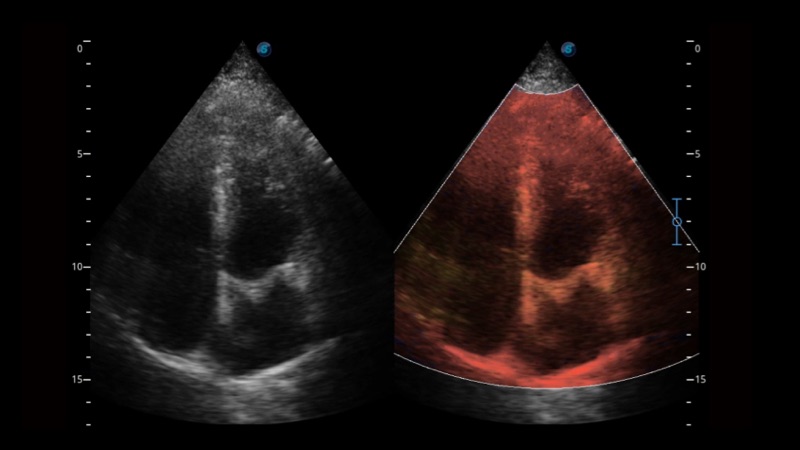

開立醫(yī)療通過不斷的技術(shù)創(chuàng)新,為大眾的生命健康提供持續(xù)關(guān)愛。P12 Plus采用全新一代超聲成像平臺,新平臺旨在將真實還原組織解剖結(jié)構(gòu)作為首要目標(biāo)。平臺采用全新集成化硬件模塊,搭載新一代芯片,系統(tǒng)性能得到大幅提升,為您的診斷提供了豐富的臨床信息。優(yōu)異的圖像表現(xiàn),豐富的探頭配置,全面的應(yīng)用功能,為您日常診斷提供了可靠的助手。

P12 Plus

彩色多普勒超聲診斷系統(tǒng)